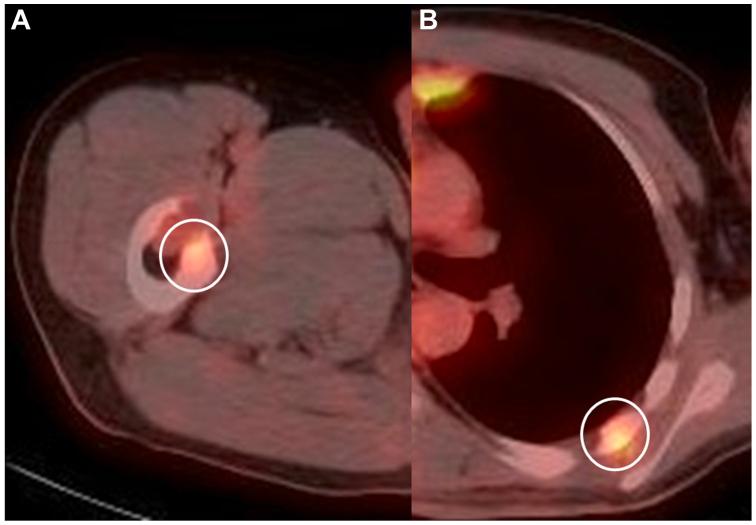

A 38-year-old man visited the otolaryngology department because of sudden onset of hoarseness a few days ago. A fiberoptic laryngoscopy revealed paralytic left vocal cord, indicating the left recurrent laryngeal nerve paralysis. Computed tomography angiography revealed a 44-mm aortic pseudoaneurysm with thrombus originating at the left subclavian artery. At total aortic arch replacement, an intimal defect was found at the origin of the left subclavian artery, where the pseudoaneurysm originated. A longitudinal ulcer-like lesion of intima was noticed. Pathology of the aortic wall revealed undifferentiated intimal sarcoma of the aorta. The aortic pseudoaneurysm developed owing to invasion of intimal sarcoma.

一名38岁男性因数天前突然出现声音嘶哑而就诊于耳鼻喉科。纤维喉镜检查显示左侧声带麻痹,提示左侧喉返神经麻痹。计算机断层血管造影显示一个44毫米的主动脉假性动脉瘤,伴有血栓形成,起源于左锁骨下动脉。在全主动脉弓置换术中,发现左锁骨下动脉起始处存在内膜缺损,此处即为假性动脉瘤的起源部位。可见内膜呈纵向溃疡样病变。主动脉壁病理检查显示为主动脉未分化内膜肉瘤。主动脉假性动脉瘤是由内膜肉瘤侵犯所致。